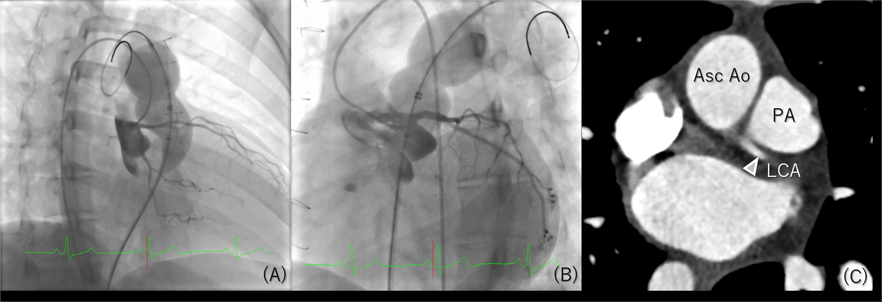

Fig. 1 Imaging modalities for assessing coronary obstruction during pulmonary valve replacement

Coronary angiogram during pulmonary valve dilation on right oblique view (A) and left anterior oblique view (B). Computed tomography showing the relationship between proximal left coronary artery and pulmonary trunk(C). Asc Ao: ascending aorta, LCA: left coronary artery, PA: pulmonary artery